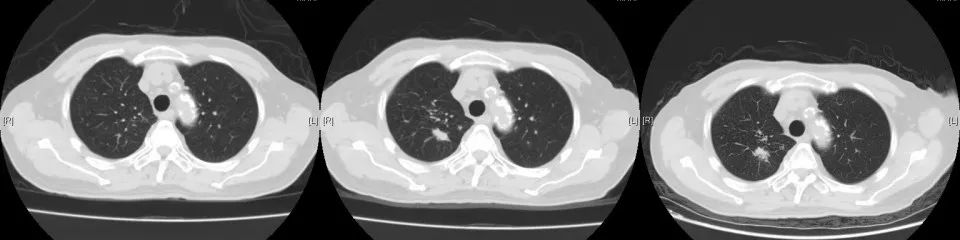

2019年9月14日复查,肺转移灶较前增大,考虑靶向耐药,我院予局部穿刺活检,病理:符合尿路上皮转移癌。2019年10月再次行NGS全基因检测,根据基因检测结果,于2019.11月开始选用“奥拉帕利”口服治疗。

2020年3月复查,病灶再次进展,参考前次基因检测结果,结合临床情况,即开始给予口服吡咯替尼80mg每日一次,2020年4月25因心梗住院治疗。停药约2周。复查示原转移灶稍增大,考虑是否与停药有关,故继续维持吡咯替尼治疗。期间多次复查,病情稳定。局部考虑缓慢进展可能。但综合考虑临床情况,仍继续维持原方案治疗。

CT变化: